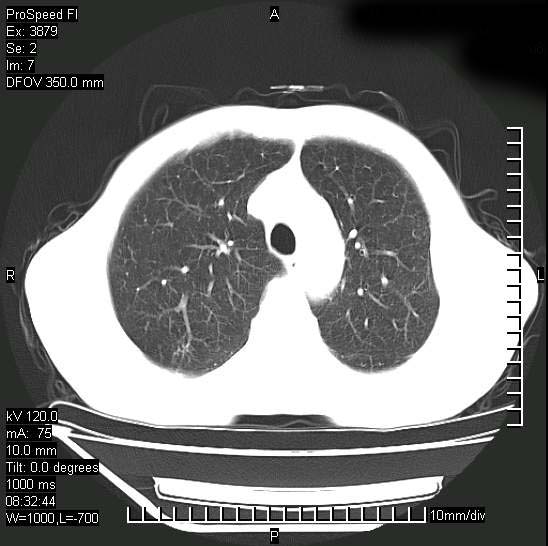

以下是引用37度在2008-6-6 11:20:00的发言:[br]1.包裹性积液,多考虑结核性;[br]2.穿刺术后改变。